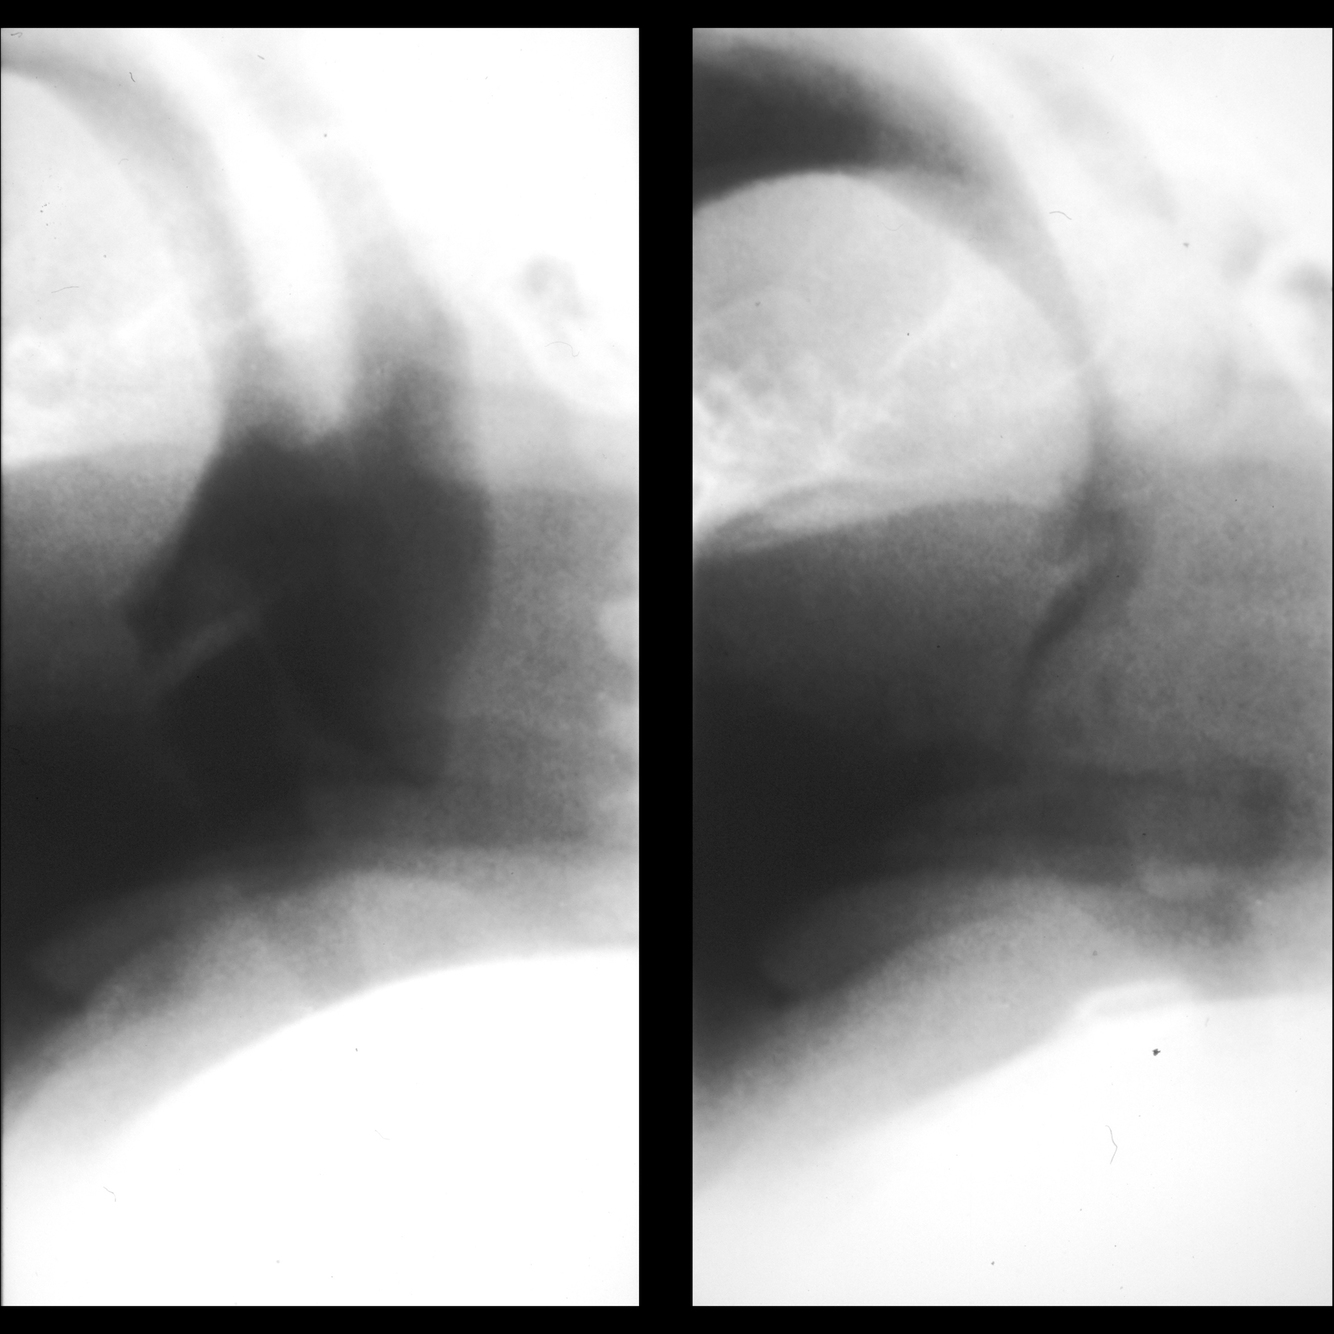

What is Laryngomalacia?

Clinical symptoms?

When does it occur?

How do you diagnose it?

Etiology: congenital cartilage abnormality in larynx

Imaging: dynamic partial supraglottic collapse of the larynx during breathing

https://pediatricimaging.org/diseases/laryngomalacia/